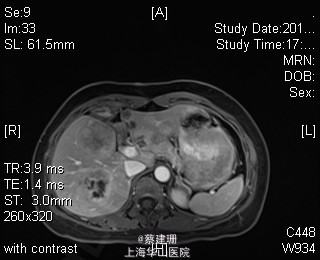

主诉:平滑肌肉瘤、肝转移癌术后,发现肝多发转移2月余。 现病史:患者3年前外院检查发现后腹膜肿瘤,外院行后腹膜肿瘤切除术后,术后病理为:平滑肌肉瘤,2013年12发现肝左叶转移癌,外院行肝左叶肿瘤切除术,术后病理为:梭行平滑肌肉瘤。2月余前患者复查发现肝脏多发转移,2015-4月肝脏MRI:肝脏多发转移。现患者无恶心、呕吐,无呕血、黑便,无皮肤巩膜黄染,无剧烈腹痛发作。现为进一步诊治收住入院。

查体:锁骨上淋巴结未扪及肿大;腹部平坦,可见陈旧性手术疤痕。未见肠型、胃型蠕动波,腹软,无压痛及反跳痛,无肌卫,肝脾肋下未及。Murphy’s 征(-),肝区叩击痛(-),肾区叩击痛(-);移动性浊音阴性。 辅查:2015-4月肝脏MRI:肝脏多发转移。

诊断 :1、多发肝转移癌 2、后腹膜平滑肌肉瘤术后 3、肝转移癌术后 处理:取右侧肋缘下切口,左侧延长,逐层切开进腹,探查腹腔:见上腹部粘连,仔细游离上腹部腹腔粘连,探查见无腹水,胃、肠、胰、脾及盆腔脏器未及异常,腹腔未见明显转移结节;肝脏无硬化。肝门淋巴结无肿大,门静脉主干无栓子。肿瘤多枚,最大两枚位于肝右叶VI段,肿瘤大小约7*6*5cm。V段肿瘤直径约5cm。左内叶肿瘤多枚,直径0.5-4cm,紧贴第一肝门。左外叶肿瘤多枚,直径1-3cm,肿块质韧,边界尚清,有包膜。术中诊断为转移性肝癌,决定行左半肝切除,肝右叶特殊肝段切除。